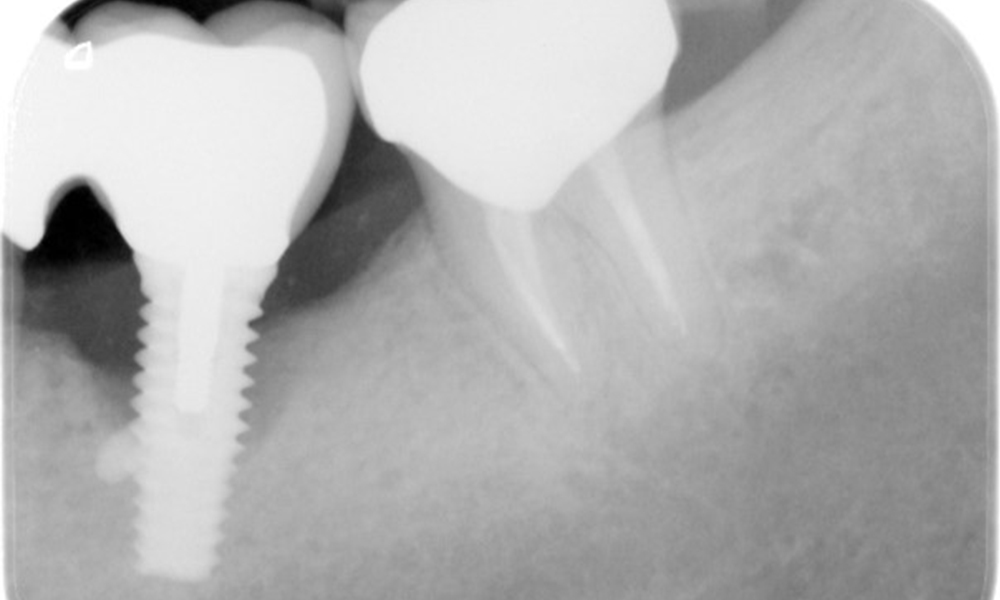

The X-ray images show the progression of bone loss in the area of the implant in region 36: dental film from 11.02.2021 (left) and dental film from 18.01.2024 (right).

OPG: 26/02/2024 Dental X-ray: 18/01/2024